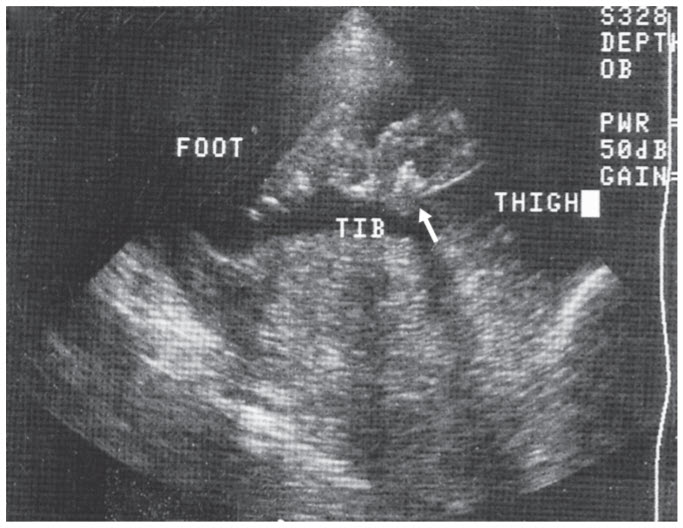

The diagnosis of osteogenesis imperfecta can be made by visualizing fractures in utero by ultrasound. The ultrasound image shows a crumpling of the tibia and fibula and curvature of the thigh such that proper extension of the foot does not occur.